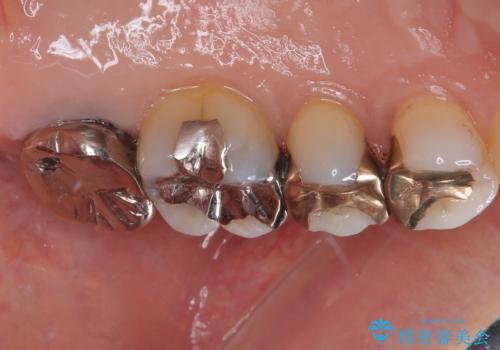

拡大鏡視野下で、金属の被せもの、虫歯の除去を行い、オールセラミッククラウンに適した形に整えました。

歯と歯茎の間に圧排糸と言われる糸を入れてシリコーン印象材にて型どりをしました。